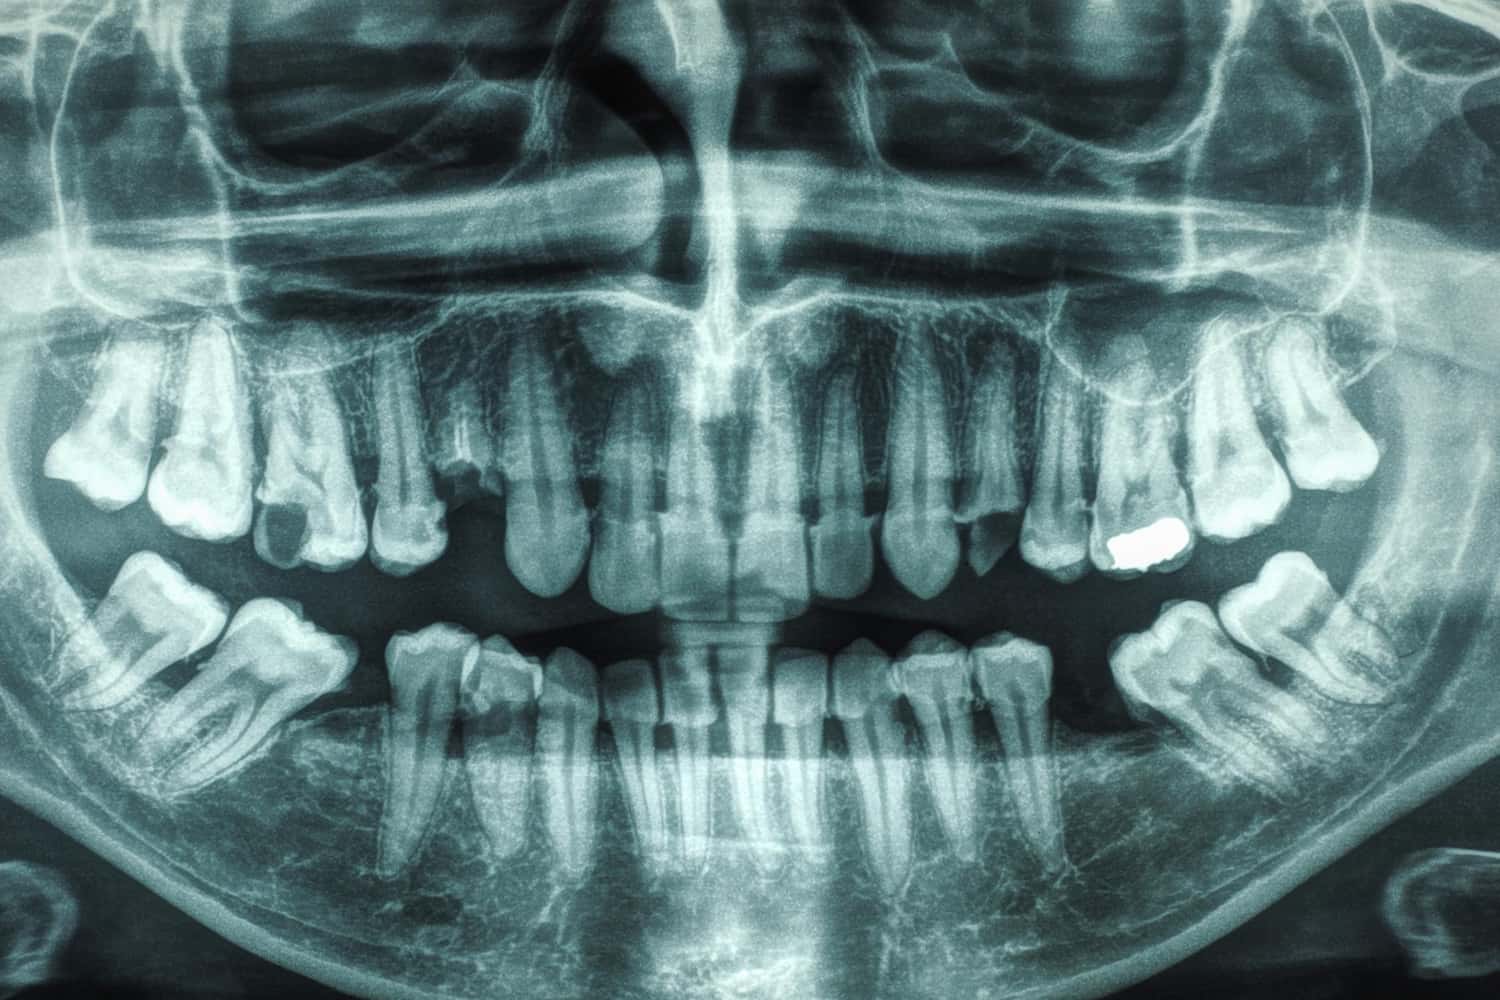

Fül-orr-gégészeti góckeresés

A fül-orr-gégészeti szűrés témakörének a teljesség igénye nélküli áttekintése során célszerű beszélni az ún. gócproblémák (például az ízületek, a szív, a húgy-ivari szervek gyulladásai, akár még a termékenységi zavarok is, a hajhullás, a köhögés, a testhőmérséklet tartós eltérései, a bőrelváltozások) esetén végzett fül-orr-gégészeti vizsgálatról is.